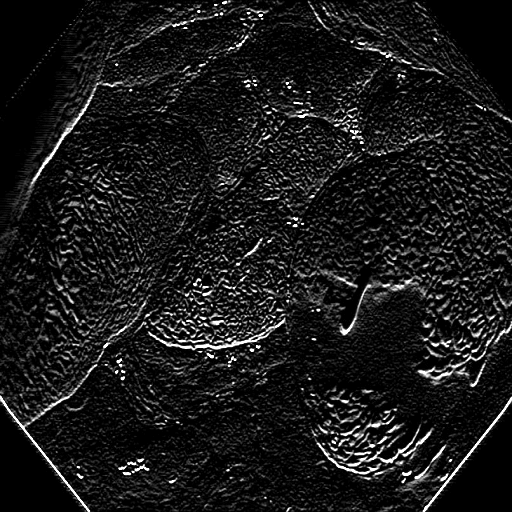

The Edge-Guided Feature Enrichment (EGFE) unit actively enhances feature representation by integrating edge knowledge into the set of features. It applies a Sobel operator to the input feature set, generating separate gradient magnitude maps for horizontal and vertical directions (Fig. 3). As illustrated in Fig. 3, the Sobel operation in a single direction captures limited information about the polyp. However, combining these maps (Fig. 3(d) and Fig. 3(h)) effectively captures polyp boundaries and enriches learned features. The final gradient magnitude map, produced using the Euclidean norm (Eq. 1), highlights regions with significant intensity changes at polyp boundaries.

Fig. 7 offers qualitative validation, showcasing MNet-SAt’s superior polyp mask generation compared to baselines across four cases. This qualitative superiority aligns with the previously established quantitative results. In the case of small polyps (first and fifth rows), all baseline methods initially appear to produce satisfactory visual results. However, upon closer inspection, they fail to maintain fine boundary details. Our framework excels in preserving polyp anatomy and topology for medium and large polyps, significantly outperforming the baseline methods. Notably, even in multiple polyps, our framework successfully captures more polyps and approximates the ground truth more closely. The primary reason for this superior performance is the EGFE module, which effectively eliminates noise in conjunction with the HMAtt module, resulting in a few false positives. Our analysis reinforces MNet-SAt’s effectiveness in handling challenging polyp scenarios (small, medium, large-scale, and multi-polyps) while suppressing non-regions of interest.